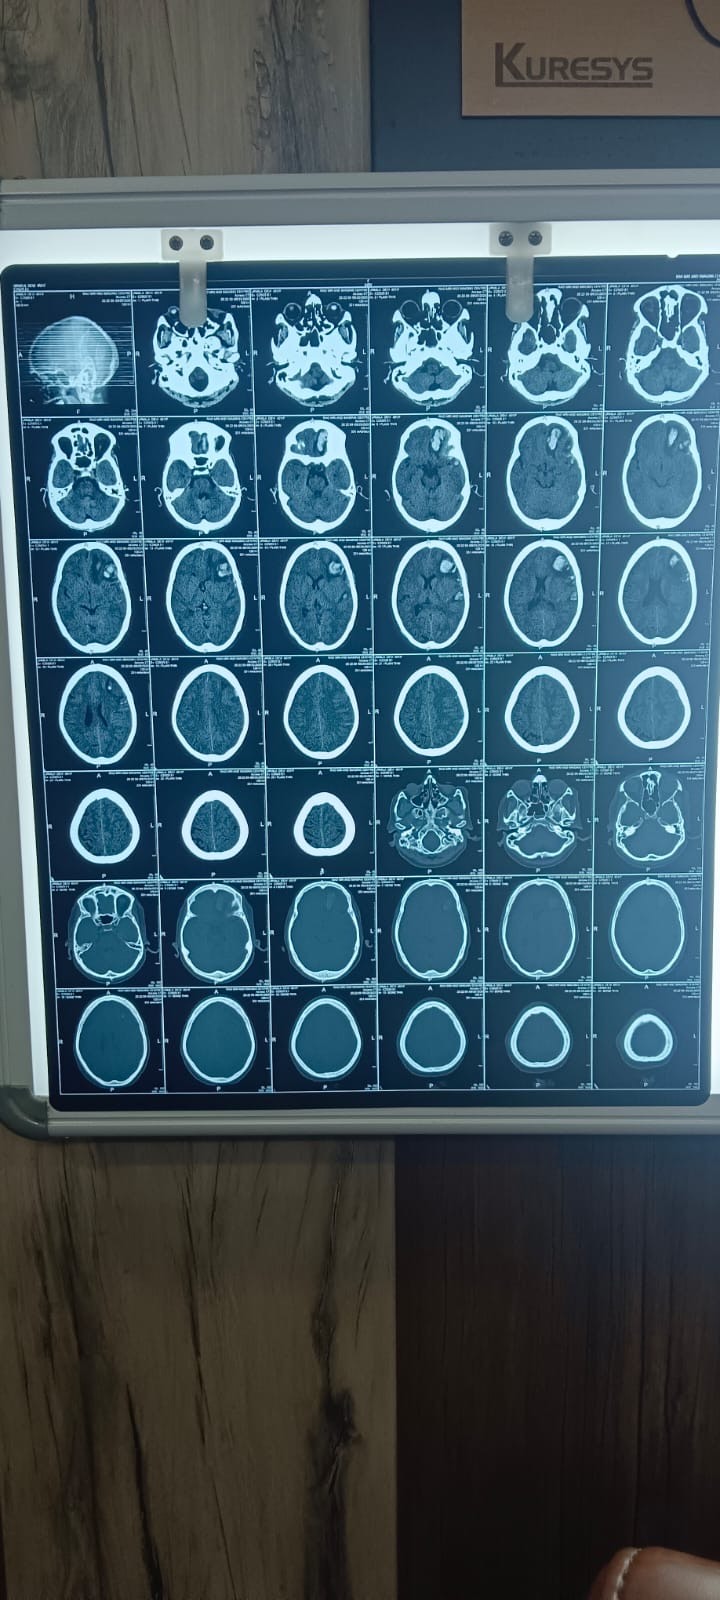

Urmila is a widow and recently met with a severe accident that caused a brain injury. She has two sons, aged 20 and 24, who together earn around $200 a month. They have already spent all their savings and are doing everything possible to support their mother’s treatment. However, the medical expenses are far beyond what they can afford.